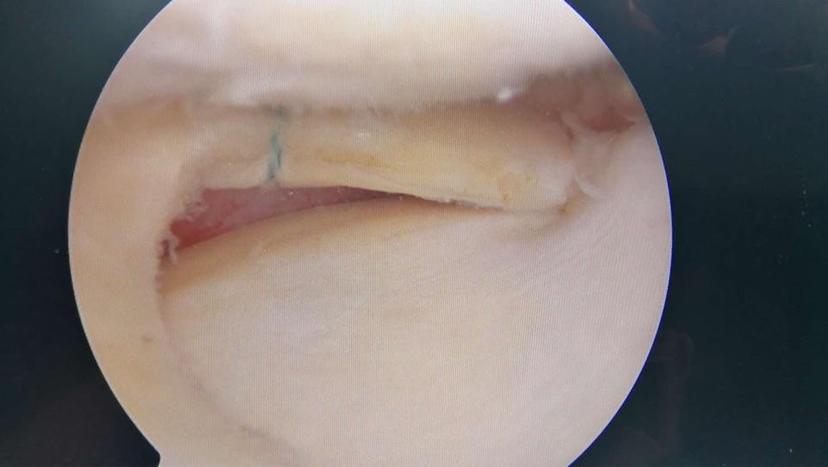

病例讲解髌骨内侧滑膜皱襞综合征

卡住的膝关节之三---内侧滑膜皱襞综合征_膝关节损伤_膝关节损伤介绍

时是膝关节内侧痛,经mri和关节镜确诊为内侧半月板损伤,内侧滑膜皱襞

2滑膜皱襞切除.png

滑膜炎镜下表现 (原创)_膝关节